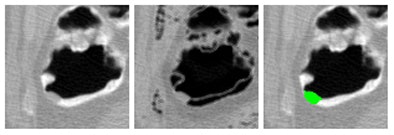

![]() |

| Application of CAD to nonlaxative case. After pseudoenhancement correction (left), tagged materials can be subtracted instantly by mapping of CT attenuations higher than 100 Hounsfield units down to the level of air (middle). The resulting residual artifacts at three-material interfaces do not affect CAD, because they look different from polyps. Leaving the artifacts in place also avoids the common problem of false-positive CAD detections from artifacts that tend to be introduced by full electronic subtraction methods. On the right, the region of a 10-mm adenoma that the CAD extracted correctly from the region is colored green. |